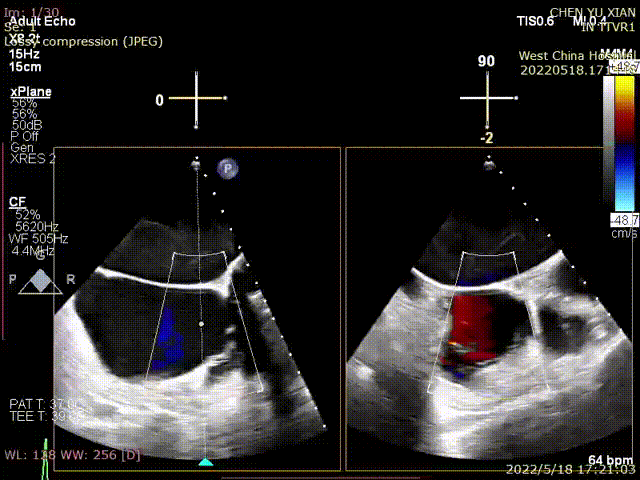

根据术前评估结果,郭应强教授团队为患者量身定制了手术策略,决定使用LuX-Valve Plus经血管三尖瓣置换系统开展手术治疗。手术在全麻下进行,采用经右侧颈静脉入路,在经食道超声和DSA的指引下调整输送器角度以达到正确位置,勾住前瓣后逐步释放盘片,盘片打开后顺利扎针,最终完成瓣膜植入,输送器撤出。术后超声提示人工三尖瓣同轴性良好,瓣架固定牢靠,无反流和瓣周漏,术后三尖瓣平均跨瓣压差为1 mmHg。

术前与术后超声